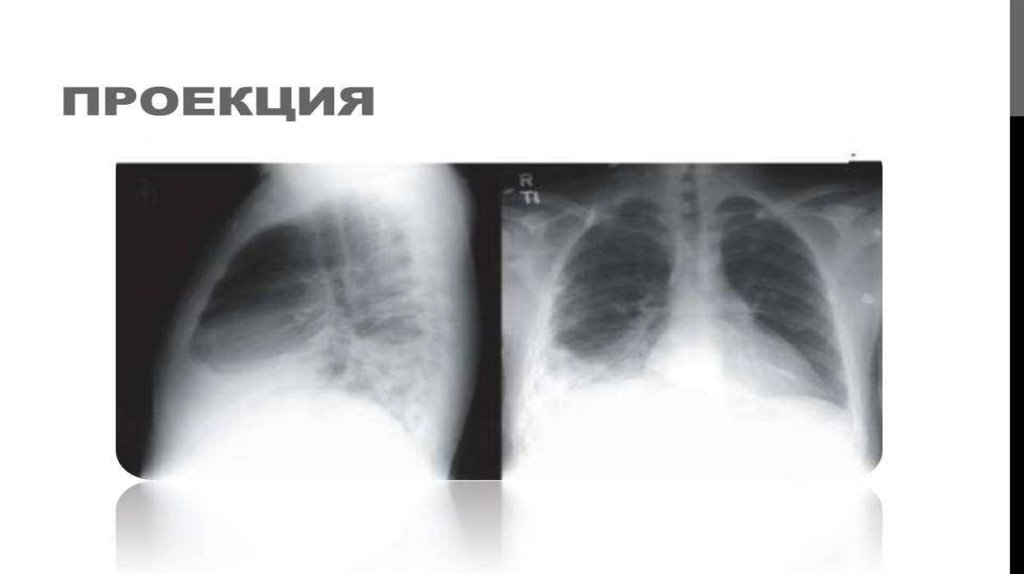

КЕУДЕ ОРГАНДАРЫНЫҢ РЕНТГЕНТ СУРЕТТЕРІ

ИНТЕРПРЕТАЦИЯЛАУ